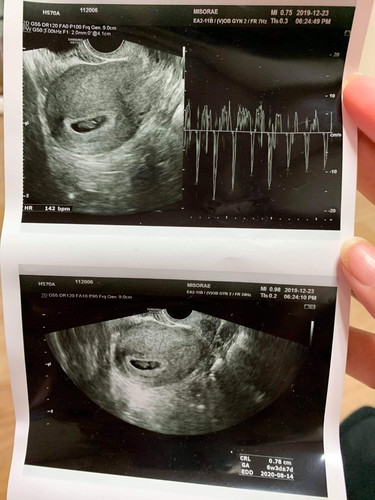

ไปซาวด์มาวันนี้ หมอบอก บอกยังไม่ได้ เลยอยากถามคุณแม่ที่มีลูกแฝดมาแล้ว ว่าแบบนี้แฝดไหมคะ ?

เห็นถุงการตั้งครรภ์ถุงเดียว มีคนเดียวคะ คุณหมอว่าไงบ้างคะ